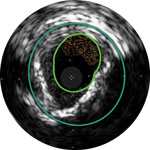

Dr. Michael Lichtenberg und Dr. Konstantinos Stavroulakis erläutern die Grundlagen der IVUS-Bildbefundung bei pAVK-Eingriffen. Anhand von Fallbeispielen demonstrieren sie den Mehrwert von IVUS bei der Beurteilung der Struktur und Pathologie erkrankter Arterien und zeigen, wie diese zusätzlichen Informationen die Behandlungsstrategie nachhaltig beeinflussen und den Behandlungsausgang verbessern können.

Dr. Stavroulakis zeigt, wie IVUS eingesetzt werden kann, um die Geometrie und Morphologie von Calcium zu verstehen, und wie diese Vorgehensweise die Behandlungsstrategie nachhaltig beeinflussen kann.

Dr. Stavroulakis erörtert, wie der Schweregrad einer pAVK durch eine reine Angiographie häufig unterschätzt wird und wie mithilfe von IVUS der prozentuale Stenosegrad und die Plaque-Belastung präzise gemessen und quantifiziert werden können.

Dr. Lichtenberg demonstriert die Empfindlichkeit von IVUS bei der Erkennung von und Unterscheidung zwischen chronischen und akuten Thromben und zeigt, wie diese Informationen die Behandlungsstrategie nachhaltig beeinflussen.